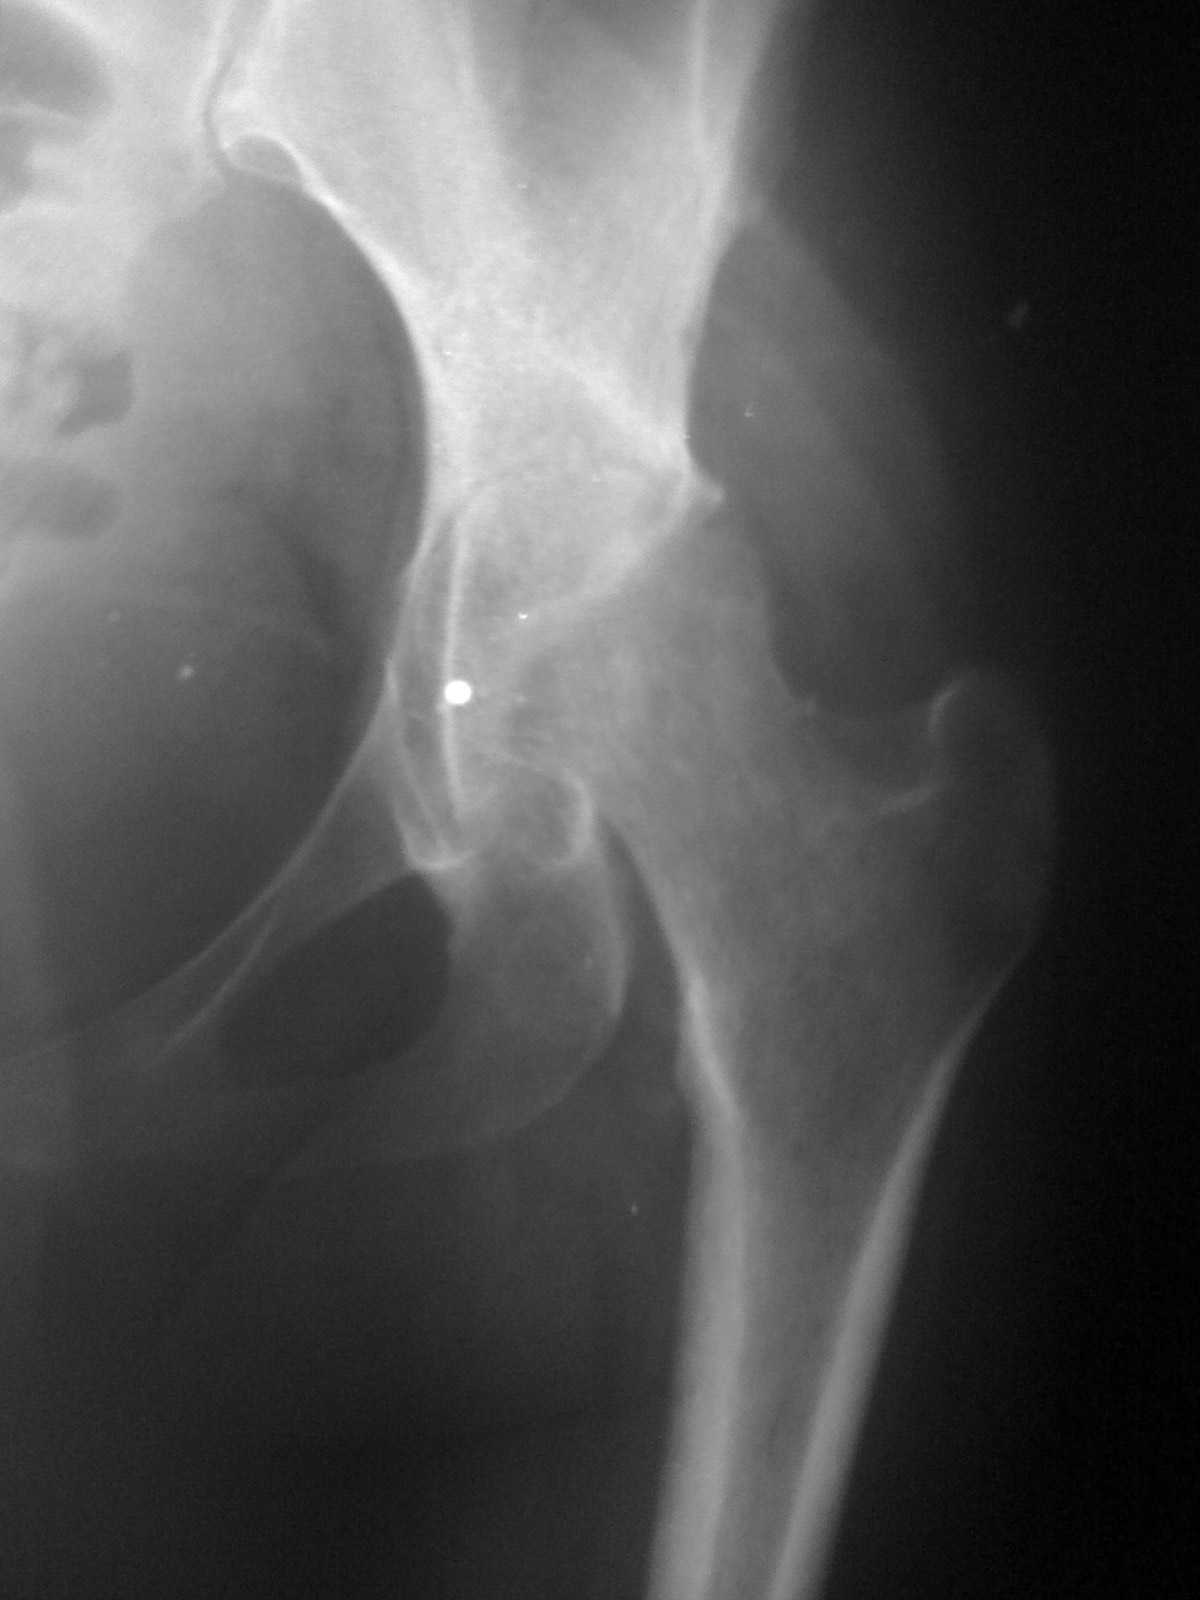

Коллеги! Пациентка 27 лет. Впервые обратилась 6 мес.назад после родов расхождение лонного сочленения, проведена консервативно.

Через 3 мес.повторное обращение по поводу болей в т\б суставе.Ходит с костылями, отведение, приведение в суставе в пределах 10*.Укорочение н\конечности на 3,0см.Непонятен механизм развития данной ситуации и какой метод лечения выбрать. Если протез то какой?